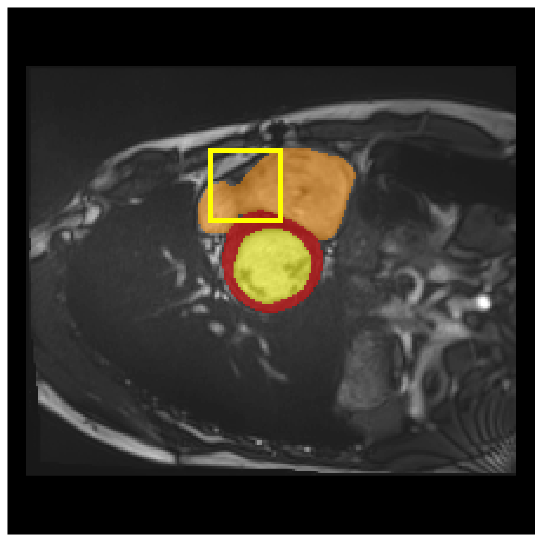

Medical image segmentation plays a critical role in various diagnostic workflows, as it enables accurate delineation of anatomical structures and pathological regions, thereby enhancing disease interpretation, treatment planning, and outcome prediction. Jang et al. [1] has demonstrated that improved segmentation performance can lead directly to reduced diagnostic error rates and increased clinician confidence. Building on the remarkable success of deep learning across diverse domains [2, 3, 4, 5], recent progress in medical image segmentation has been primarily driven by deep learning. Since the introduction of U-Net [6], segmentation methods have rapidly evolved, with convolutional neural networks (CNN)-based models [7, 8, 9] and Transformer-based models [10, 11, 12] showing superior performance in computed tomography (CT) and magnetic resonance imaging (MRI) segmentation. However, various challenges such as blurriness, noise, and low contrast often hinder the accurate diagnosis of diseases. Applying various image enhancement techniques to generate an enhanced image from the input can alleviate this problem, as existing methods have demonstrated improved segmentation accuracy [13, 14, 15]. Nevertheless, input images may unintentionally lose crucial information contained in the original image during enhancement. As a result, the segmentation model suffers from performance degradation (Fig. 1(a) and (b)). Therefore, we argue that it is crucial to leverage the advantages of both the original and enhanced images through image fusion strategies.

4.3.2 Visual Comparisons

Visualization of our method on the Synapse and ACDC datasets is shown in Fig. 3(a) and Fig. 3(b). For the Synapse dataset illustrated in Fig. 3(a), FCT failed to accurately segment SM and GB, while MERIT achieved precise segmentation of SM but struggled with GB. In contrast, our method achieved accurate segmentation of both SM and GB. Regarding the ACDC dataset shown in Fig. 3(b), while previous methods achieve comparable segmentation of the Myo and LV to the GT, they exhibit noticeable errors on the RV, including invasion into adjacent organs and misrecognition. On the other hand, our method accurately segments across all three structures Myo, LV, and RV, performing as precisely as the GT. We demonstrate the superiority of our method quantitatively and qualitatively.